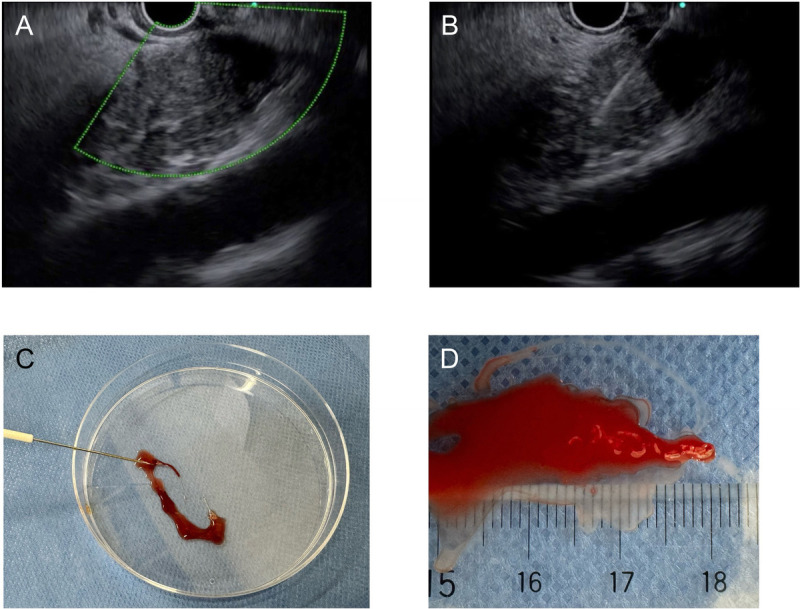

Methods: In the ROSE group, if an adequate sample was obtained to diagnose by on-site evaluation, EUS-FNB was stopped. If cytological results were insufficient or indeterminate, EUS-FNB was repeated. In the macroscopic on-site evaluation (MOSE) group, if a 4-mm length of visible core tissue was obtained, EUS-FNB was finished. If visible core tissue was not obtained or was less than 4 mm in length, a second puncture was attempted.

Results: One hundred seventy-one patients were randomized, 85 to the ROSE group and 86 to the MOSE group. In the MOSE group, diagnostic sensitivity and accuracy were 94.4% and 91.8%, respectively, for visible core tissue and 80.6% and 70.0%, respectively, for red tissue. Finally, overall diagnostic sensitivity and accuracy were 97.1% and 95.3%, respectively, in the ROSE group and 95.8% and 95.3%, respectively, in the MOSE group. Although there were no significant differences regarding adverse events between groups, the mean number of punctures was significantly lower in the MOSE group than in the ROSE group (1.47 vs. 1.20, P = 0.0171).